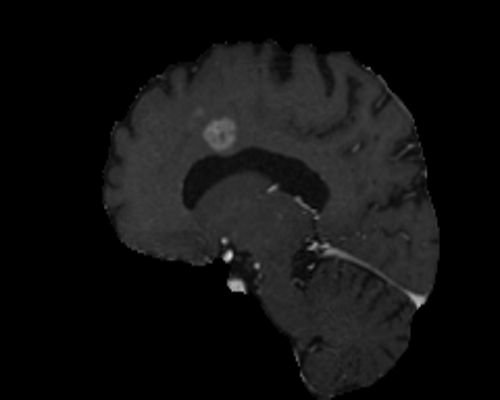

For segmentation, we employ the zero-shot method MedCLIP-SAMv2 [koleilat2024medclip, koleilat2024medclipsamv2]. It works by computing activation maps from a pre-trained CLIP model, and using them as query for the Segment Anything Model (SAM) [kirillov2023segment]. Activation maps are computed using Multi-Modal Information Bottleneck Attribution (M2IB) [wang2023visual], using a target image and a query prompt. Here, we aim at improving the quality of the activation maps on different concepts by leveraging KT. This, in turn, should result in a higher accuracy of the final segmentation. We target four different segmentation tasks: lung nodules segmentation on CT images (UnitoChest), pneumothorax segmentation on CXR images (SIIM Pneumothorax), breast nodule segmentation on ultrasound images (UDIAT), and glioma segmentation in MRIs (BraTS23).

The overall results across all segmentation tasks are presented in Tab. 7. The captions used for inversion are reported in the supplementary material. To compute the M2IB activation maps on the fine-tuned models, we employ descriptive prompts as suggested in [koleilat2024medclipsamv2]. The prompts are reported in Tab. 7 as P1 to P4 for each task. We also report reference results of MedCLIP-SAMv2 on each task. Compared to the original setting of MedCLIP-SAMv2, lung nodules and lung pneumothorax are completely novel concepts. There is also a slight difference in the brain glioma class compared to the original brain tumor task, explained in the supplementary file. We employ three metrics to assess the segmentation quality, namely the Dice-Sørensen Coefficient (DSC), Normalized Surface Distance (NSD), and Intersection over Union (IoU). We report results with different values of fine-tuning learning rate. We can observe an increase in segmentation metrics across all tasks, notably in breast ultrasound (NSD 59.44% to 61.56%) and brain MRIs (NSD 20.97% to 22.26%). For lung nodules and pneumothorax, the improvement is less pronounced, probably because the novelty of the task makes improving more difficult in the MedCLIP-SAM setting. We report some visual examples on breast tumor segmentation in Fig. 5, showcasing the improvements of KT.

Results of knowledge transfer on MedCLIP-SAMv2 with different values of learning rate are shown in Tab. 14. We report illustrative examples of the improvements achieved by knowledge transfer in Fig. 11 and Fig. 12. The captions used for inversion for segmentation can be found in Tab. LABEL:tab:captions-segmentation.

Differences in downstream tasks

As said in the main text, lung nodules and pneumothorax segmentations are novel tasks on which MedCLIP-SAMv2 was not pre-trained. Regarding brain tumors, we employ the BraTS 2023 glioma dataset, which contains brain gliomas in adult patients. With respect to the original performance reported in [koleilat2024medclipsamv2] on brain tumors, we notice a significant gap. However, the preprocessing of the images is quite different, as data from BraTS 2023 is more heavily preprocessed (e.g. skull stripping) than in [koleilat2024medclipsamv2]. We were not able to compare MedCLIP-SAMv2 on the original data, as, at the time of writing, details about the data split are missing.